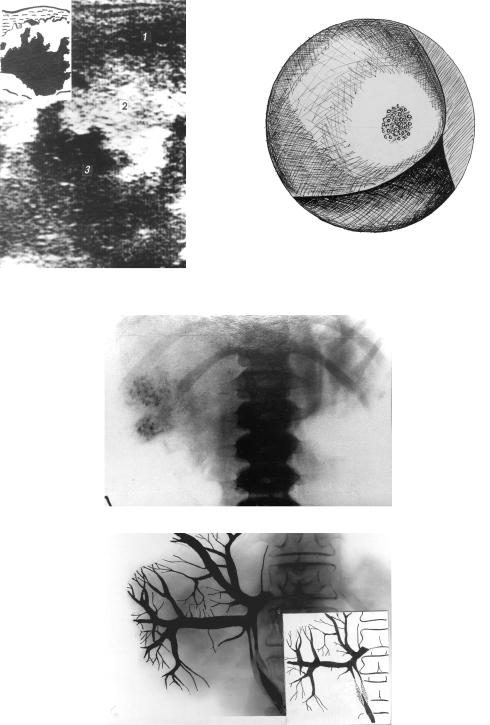

Понимание кавернозного туберкулеза почки